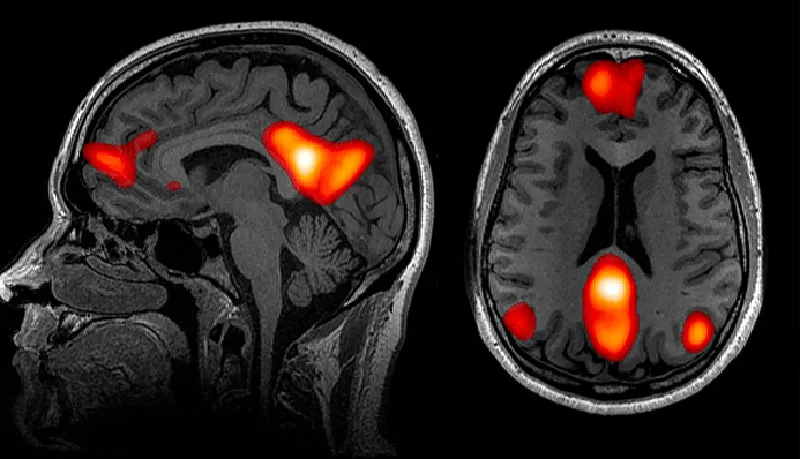

有趣的是,他们于2020年发表在《自然通讯》杂志上的研究结果显示 [12] , 与孤独感对应的大脑区域是默认网络 (default network)。他们发现, 在孤独人群中,默认网络不仅体积更大,而且与大脑其他部位的连接也更加紧密。

直到20多年前,科学家们才知道有默认网络的存在。它是一个耗能大,且当个体处于精神漫游状态时会被激活的大脑区域。此外,之前的研究显示,默认网络似乎与人类进化过程中形成的许多独特能力有关,如语言、预测未来和因果推理等能力。比如,在日常生活中,当我们想起他人时,或试图揣测他人意图时,默认网络就会被激活。

上述研究的结果与心理学家之前的发现不谋而合,即处于孤独状态的人往往会在脑海中幻想社交互动,容易念旧,甚至会将宠物拟人化,例如,把猫当人类一样进行交谈。布兹多克(Bzdok)表示:“这些行为都需要默认网络的参与。”

▷ 与默认网络相关的一些大脑区域。来源:John Graner, Terrence Oakes, Louis French and Gerard Riedy